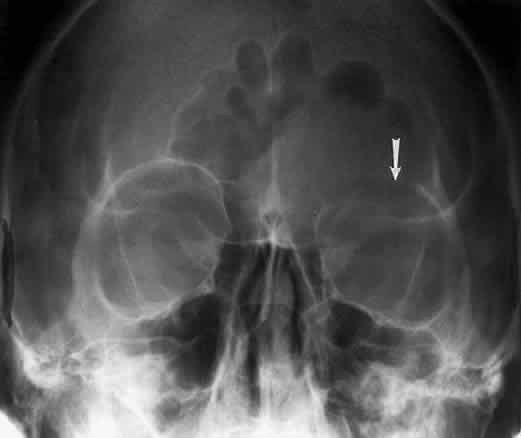

The orbital floor consists of the maxillary, zygomatic, and palatine bones. The floor is thinnest medial to the infraorbital canal, which is the location of most orbital floor fractures (Fig. 7). As mentioned earlier, the floor slopes upward from the lateral to the medial wall. The floor extends toward the orbital apex but does not reach the apex. This orientation of the floor makes frontal projections more informative than the lateral projection.

Fig. 7. A patient involved in a motor vehicle accident who sustained a right orbital floor fracture. Soft tissue density (arrow) located in the roof of the maxillary sinus. Disruption of the orbital floor is seen at the fracture site.

Waters view gives the best image of the anterior and middle portion of the floor. This is possible because extension of the neck brings the floor into a position that is tangential to the x-ray beam. The floor is represented by the most inferior radiopaque line, whereas the orbital rim will be the line above it.10 The vertical distance between these lines should be approximately 1 cm.19 This relationship between the floor and the orbital rim should be symmetric between the two orbits. Any asymmetry should suggest a fracture of the orbital rim or floor.